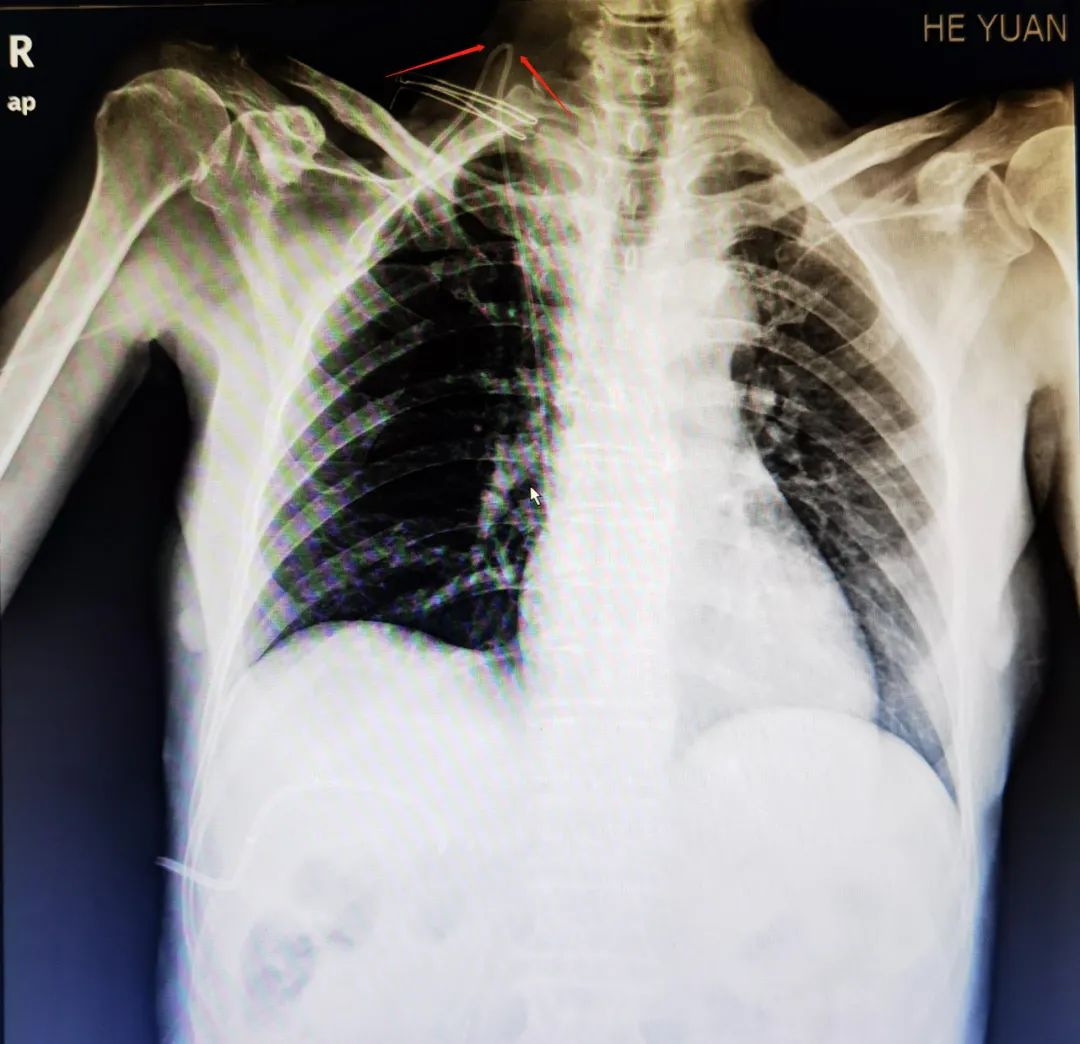

患者颜某某,确诊胰头中低分化腺癌、梗阻性黄疸,右侧颈内静脉留置胸壁输液港,入院行术前化疗。护士使用输液港前常规检查发现输液港不通畅,进一步行B超检查发现输液港颈静脉段附壁血栓形成,血栓大小约5.2mm×2.5mm,针对上述问题,常规处理是抗凝治疗后拔除输液港,但拔除输液港意味着需要重新置入输液港或置入PICC建立静脉输液通路,花费大且可能延误治疗。静疗护理专家李柳英主任护师了解情况后,查阅了患者的影像学检查资料,发现患者的静脉导管行径有“打折”痕迹(图1红色箭头标识部位),初步判断是导管打折造成的导管不通,并非局部血栓形成堵塞静脉导管,建议手术调整静脉导管走行以恢复导管功能,经手术处理后,患者的输液港恢复通畅,可正常使用,生命线重新开通。

红色箭头为患者输液港打折处